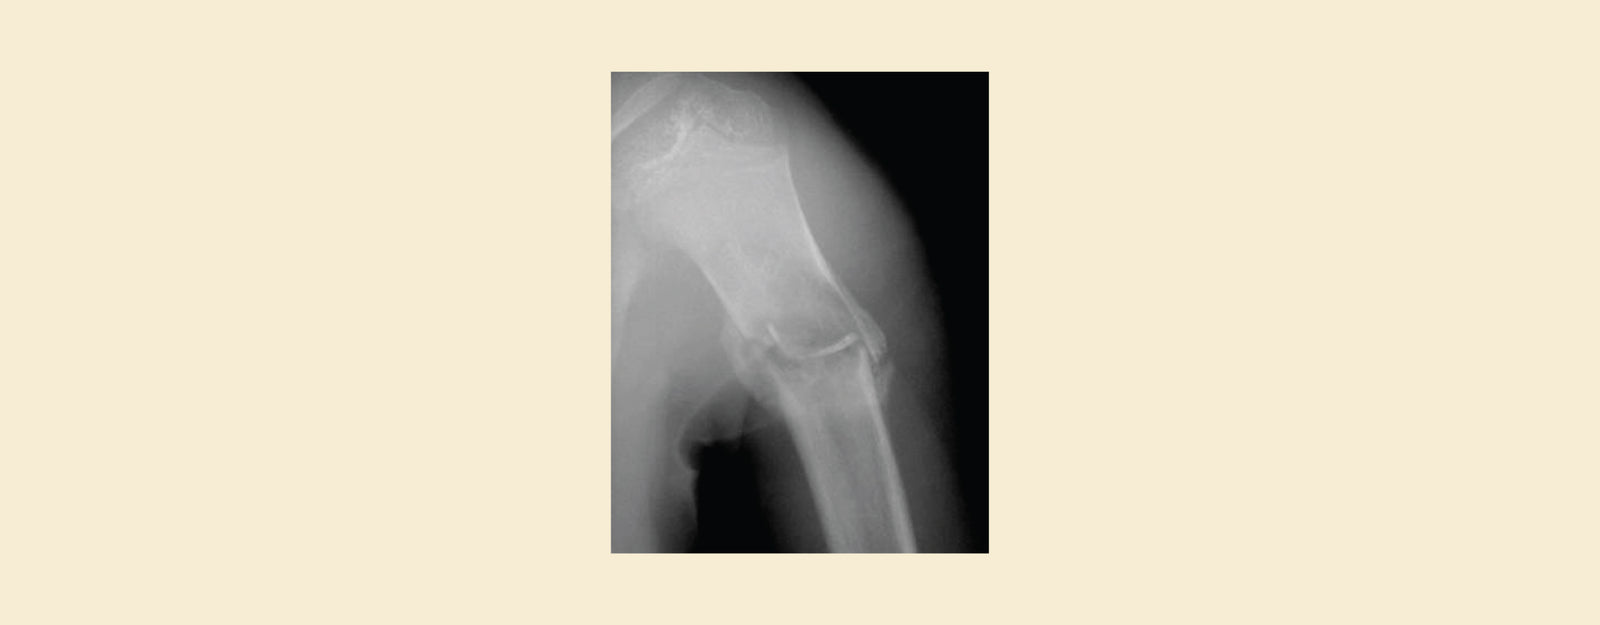

- X-rays show a single, well-defined, fluid-filled cavity (unicameral, meaning "one chamber") in the bone's middle section (metaphysis). The surrounding bone may have a narrow ring of reactive bone development.

- X-rays reveal a more expansive, multi-chambered (multicameral) fluid-filled cavity with a thinner, occasionally bulging, bony exterior. May be eccentric (off-center) within the bone.